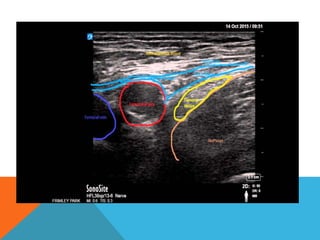

• Transverse probe position, initially over femoral artery at or immediately

to inguinal crease

• Slide transducer laterally

• Identify HYPERECHOIC oval or triangular shaped femoral nerve lateral

to the artery on the iliopsoas muscle, under fascia iliaca

• Femoral nerve triangle created by the femoral artery medially, fascial planes

anteriorly and the iliopsoas muscle posteriorly

• Place needle between iliopsoas muscle and its facia, 1 cm lateral to the

nerve.

• Inject LA at this position resulting in a spread of LA around the nerve